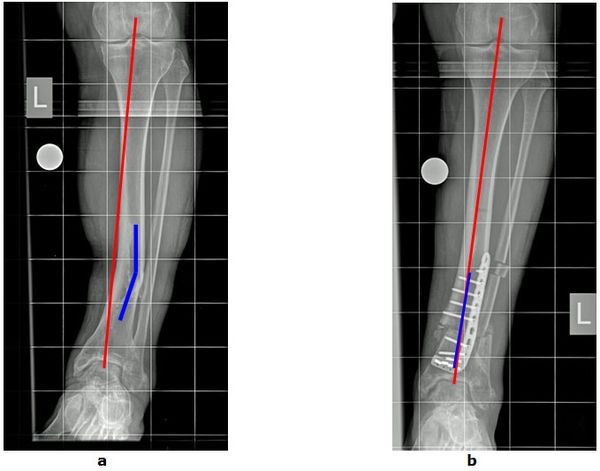

Abb.2: a O-Bein Fehlstellung durch Knick im Unterschenkel (blaue Linie) nach einem Knochenbruch. Der Patient klagt durch die Fehlbelastung über Schmerzen im Sprunggelenk. Eine Arthrose ist bereits eingetreten.

b Begradigung der Beinachse durch eine gelenknahe Knochenumstellung mit Entlastung der Arthrose.